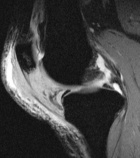

41 year old male c/o left knee mass and swelling. He has a history of T-cell lymphoma diagnosed several years ago. He has been in remission for almost seven years. Six months prior, he began to experience left knee pain and swelling.

Zoom image: Radiological image Radiological image.